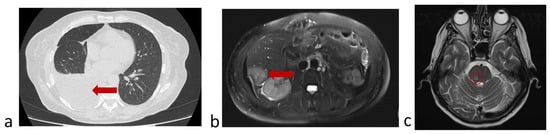

3.6.2. A Clinical Example Demonstrating a Unfavorable Outcome of the Disease and the Evolution of the Number of CTCs Detected in the Peripheral Blood